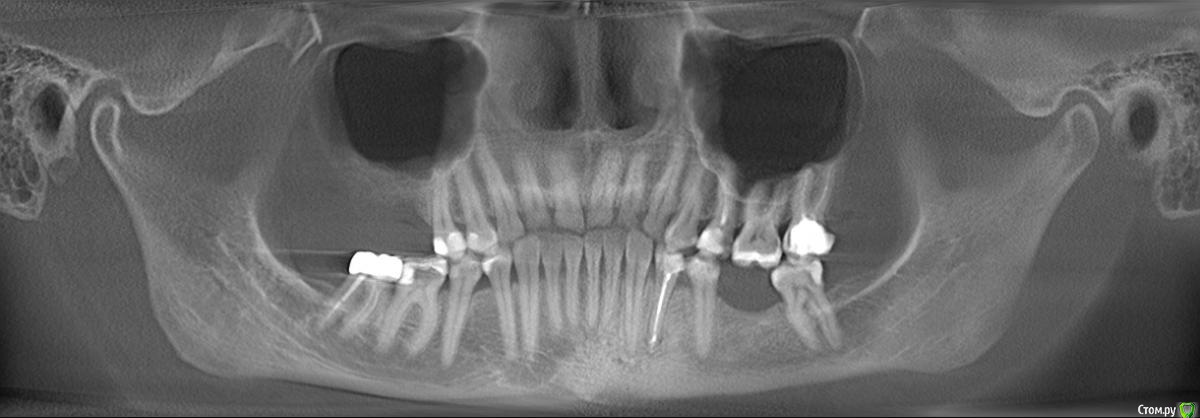

wladdX Опубликовано 27 февраля, 2019 Поделиться Опубликовано 27 февраля, 2019 (изменено) Скриншоты Сколько успел Изменено 27 февраля, 2019 пользователем wladdX Ссылка на комментарий

red_butler Опубликовано 27 февраля, 2019 Поделиться Опубликовано 27 февраля, 2019 соустье нужно посмотреть, но предварительно - не вижу препятствий для проведения открытого синуслифта Ссылка на комментарий

wladdX Опубликовано 27 февраля, 2019 Поделиться Опубликовано 27 февраля, 2019 Похоже, я загрузил скрины другого пациента (на диске записаны 2 исследования), исправляюсь. Ссылка на комментарий

kramer Опубликовано 27 февраля, 2019 Поделиться Опубликовано 27 февраля, 2019 Закрытый синус-лифт + 10 мм имплантат Ссылка на комментарий

red_butler Опубликовано 27 февраля, 2019 Поделиться Опубликовано 27 февраля, 2019 8 мм имплант и закрытый синус без графта Ссылка на комментарий

колесников Опубликовано 3 марта, 2019 Поделиться Опубликовано 3 марта, 2019 У вас речь идёт об одном импланты в области 16. Одиночный короткий Имплант не рекомендуется ни одним из производителей имплантов. Открытый синуслифтинг не показан из за особенностей строения пазухи в этой области,показан закрытый. Так же рекомендовал бы Астра тек,4.5х9. А также:дистализация 17го и имплантация в области 47.. либо удаление 17го,имплантация 17,16,47 Ссылка на комментарий